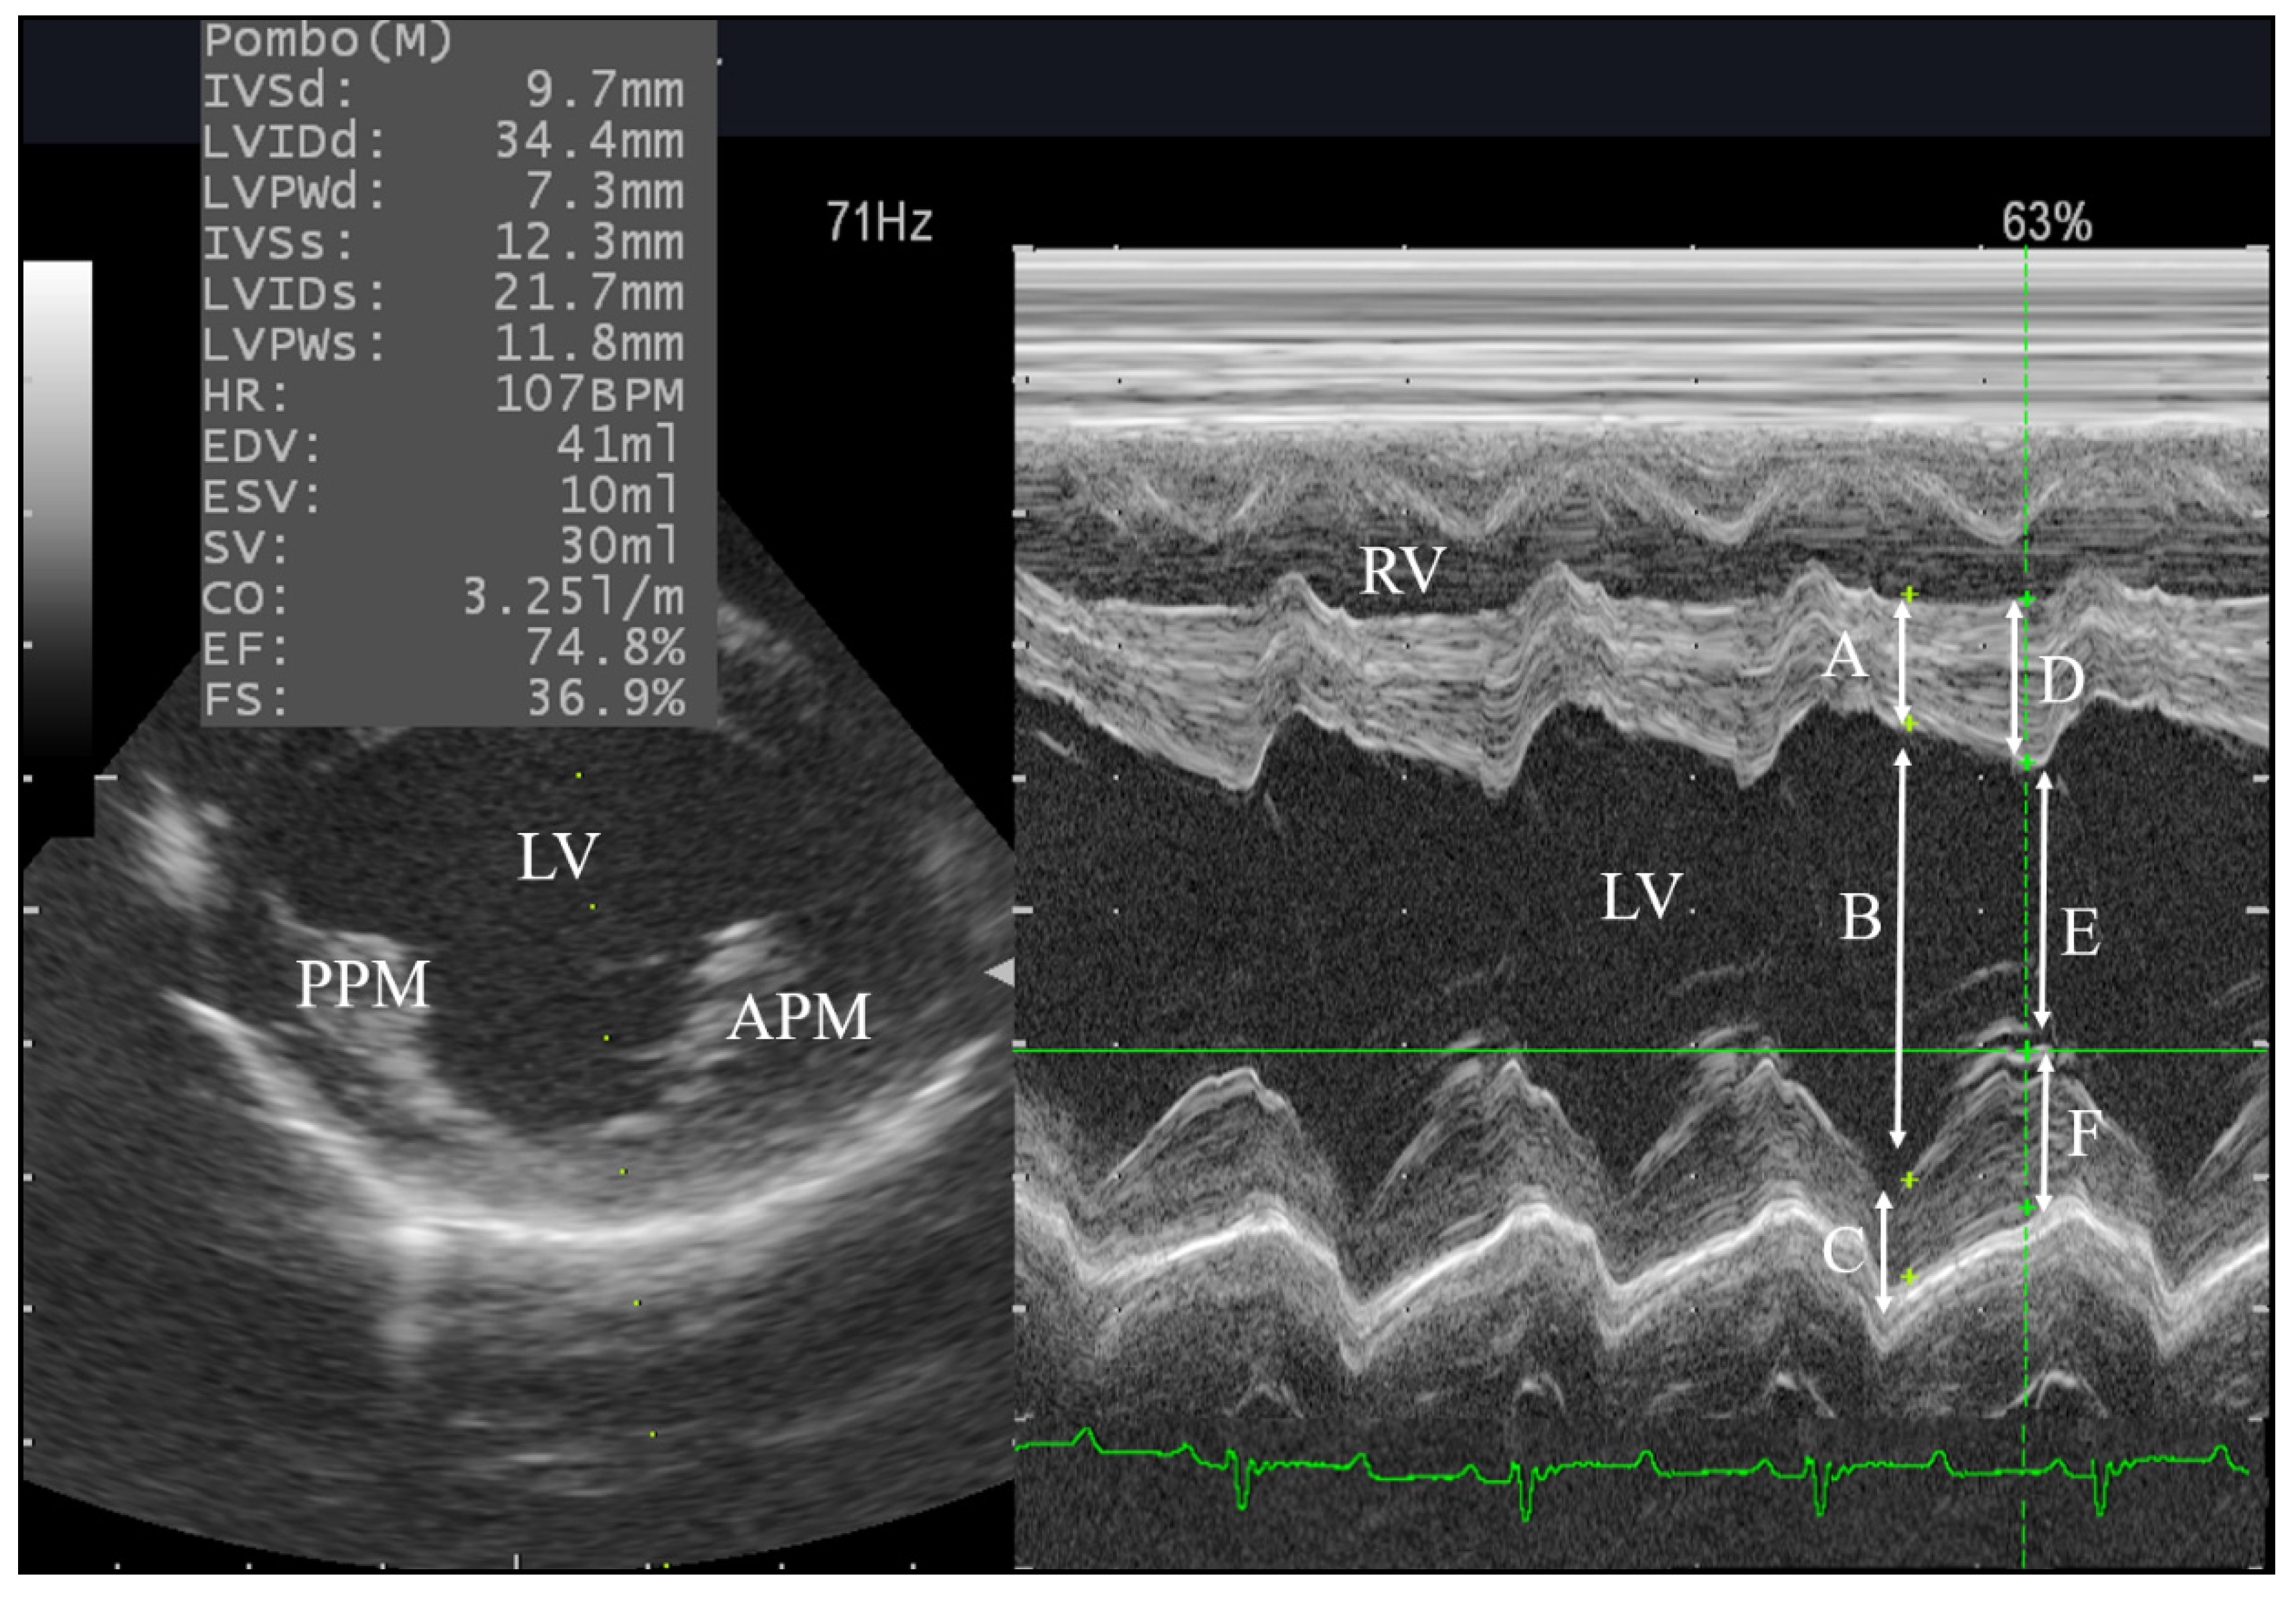

2.4. Conventional Echocardiography

3.4. Left Side Echocardiography

| LV measurements | IVSd | mm | 8.084 | 1.218 | >0.10 | ns | 15.00 |

| LVIDd | mm | 33.1 | 2.896 | >0.10 | ns | 8.75 | |

| LVPWd | mm | 7.944 | 1.369 | >0.10 | ns | 17.24 | |

| IVSs | mm | 12.32 | 0.819 | >0.10 | ns | 6.65 | |

| LVISd | mm | 21.09 | 2.454 | >0.10 | ns | 11.64 | |

| LVPWs | mm | 12.36 | 1.948 | 0.052 | ns | 14.76 | |

| HR | pbm | 106.5 | 10.67 | >0.10 | ns | 10.02 | |

| EDV | mL | 37.15 | 9.268 | >0.10 | ns | 24.95 | |

| ESV | mL | ml | 3.106 | >0.10 | ns | 30.91 | |

| EF | % | 70.28 | 7.017 | >0.10 | ns | 9.99 | |

| FS% | % | 35.45 | 4.157 | >0.10 | ns | 11.73 | |

| IVSd | mm | 7.5 ± 0.5 | 8.0 ± 0.2 | 0.38 |

| LVIDd | mm | 33.6 ± 1.4 | 34.4 ± 1.1 | 0.64 |

| LVPWd | mm | 7.9 ± 0.6 | 7.2 ± 0.3 | 0.24 |

| IVSs | mm | 13.3 ± 0.2 | 12.3 ± 0.2 | 0.02 * |

| LVISd | mm | 19.3 ± 1.5 | 21.3 ± 0.9 | 0.15 |

| LVPWs | mm | 13.0 ± 0.7 | 12.8 ± 0.7 | 0.73 |

| EDV | mL | 39.5 ± 4.8 | 41.7 ± 3.9 | 0.72 |

| ESV | mL | 8.7 ± 1.7 | 10.1 ± 1.3 | 0.30 |

| EF | % | 75.7 ± 4.6 | 74.2 ± 2.9 | 0.71 |

| FS% | % | 41.5 ± 2.9 | 37.8 ± 2.6 | 0.07 |